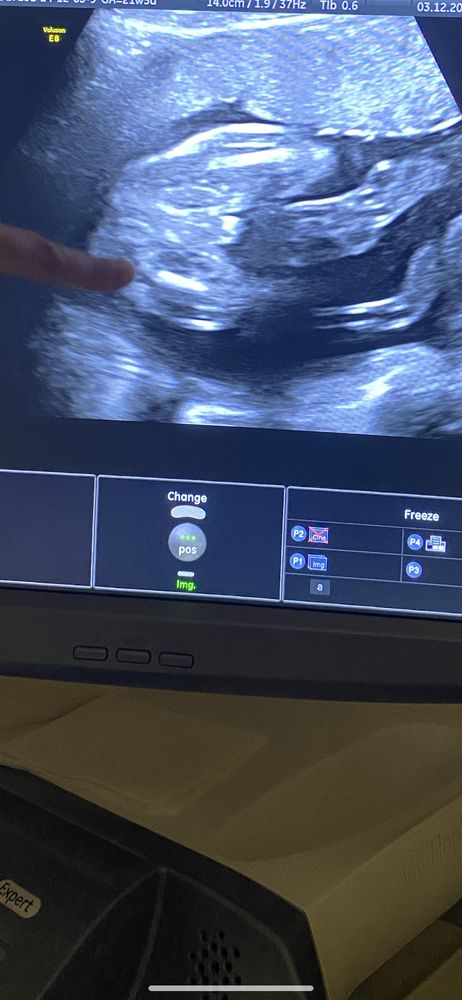

Могу ошибаться, конечно, но вижу мальчика))

Пацан. Мне на аналогичном фото узи даже обвеои причинное место и написали рядом "он - мужчина" 😂